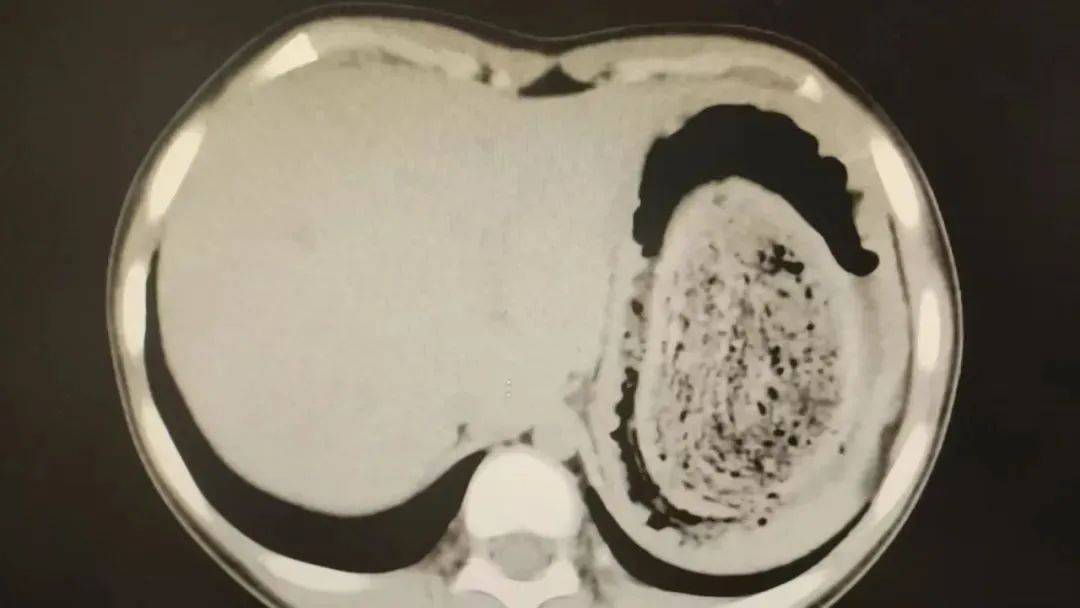

在胃镜帮助下,妮妮胃里的情况逐渐明了皇冠信用网登2。一个滚圆黑色的毛发球混合着食物残渣占据整个胃腔,这些头发相互缠绕形成一个实心的“发石”,此外胃里还有一个鸡蛋大小的溃疡。

10岁女孩园园(化名)因持续3天的上腹痛伴呕吐被紧急送医皇冠信用网登2。影像学检查结果显示,她的胃部存在一个巨大的团块状阴影,初步怀疑为异物堵塞。据家长回忆,园园从1年前开始就有偷偷吃头发的习惯,但家人并未重视,直到这次症状严重才意识到问题的严重性。

2024年10月,11岁女孩欢欢(化名)因腹痛难耐紧急送到医院,而就在两个月前,欢欢的父母发现她在拔自己的头发,偷偷吃掉皇冠信用网登2。经检查,医生发现她胃腔和肠管里有大块的毛絮状结石,几乎占据整个胃部。最终,一块长38厘米、宽15厘米、厚10厘米的毛发结石被取出。